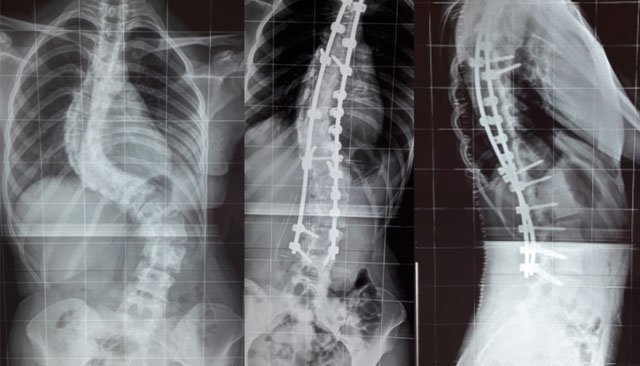

Une équipe du service de traumato-orthopédie pédiatrique de l’hôpital mère-enfant relevant du CHU Hassan II Fès a réalisé avec succès, des opérations de la scoliose chez cinq malades bénéficiant du Régime d'assistance médicale (Ramed).

Ces interventions chirurgicales, qui ont été réalisées par cette équipe conduite par le Pr Abderrahmane Afifi en collaboration avec un expert français de l’hôpital Robert Debré, ont bénéficié à quatre filles et un garçon, âgés de 15 à 18 ans.

Les dispositifs onéreux (de 60.000 à 150.000 DH) et le caractère lourd de ce type d’interventions, limite le recours à cette chirurgie qui demeure une quasi-exclusivité des CHU au Maroc, indique le ministère de la Santé dans un communiqué.

Les premières chirurgies de la scoliose ont été réalisées avec succès au CHU Hassan II en 2012. La particularité de ces interventions réside dans le matériel et dispositifs médicaux ultra-sophistiqués utilisés qui permettent une meilleure correction de la colonne vertébrale.

La scoliose, qui est une déformation permanente de la colonne vertébrale liée à une torsion des vertèbres les unes par rapport aux autres, apparaît le plus souvent pendant l'enfance, mais peut aussi survenir à l'âge adulte.